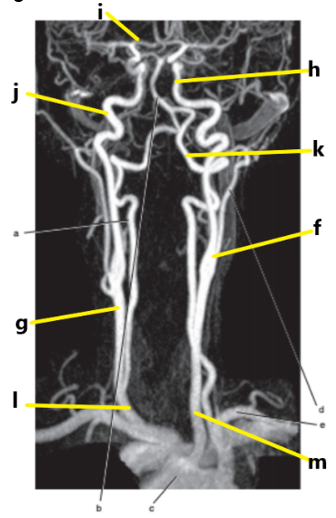

What is letter l ?

Common carotid

What is letter e ?

Subclavian artery

What is letter i ?

Anterior cerebral artery

What is letter m ?

Common carotid artery

What is letter j ?

Internal carotid artery

What is letter g ?

What is letter a ?

Vertebral artery

Aortic arch

What is letter b ?

What is letter h ?

Internal jugular vein

What is letter k ?

Basilar artery

Carotid sinus/bifurcation